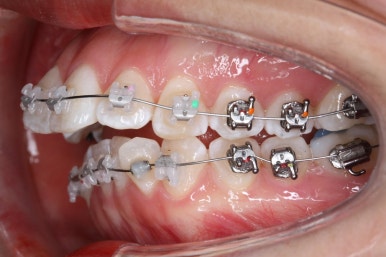

점점 가지런해지고 있습니다.

아래 앞니는 자리가 많이 부족했기 때문에 장치를 제대로 못 붙인 치아가 있고, 자리부터 확보해주고 있습니다.

윗니는 발치교정이라 하더라도 치아를 바로 뽑지는 않습니다.

최대한 쓸만큼 쓰고, 조금 움직여놓고 해야 수월하게 아프지 않고 뽑을 수 있습니다.

윗니는 발치를 했고, 잇몸뼈에 미니스크류를 식립하여 앞니를 뒤로 당겨넣고 있습니다.

아랫니는 아직 덜 가지런해졌네요.